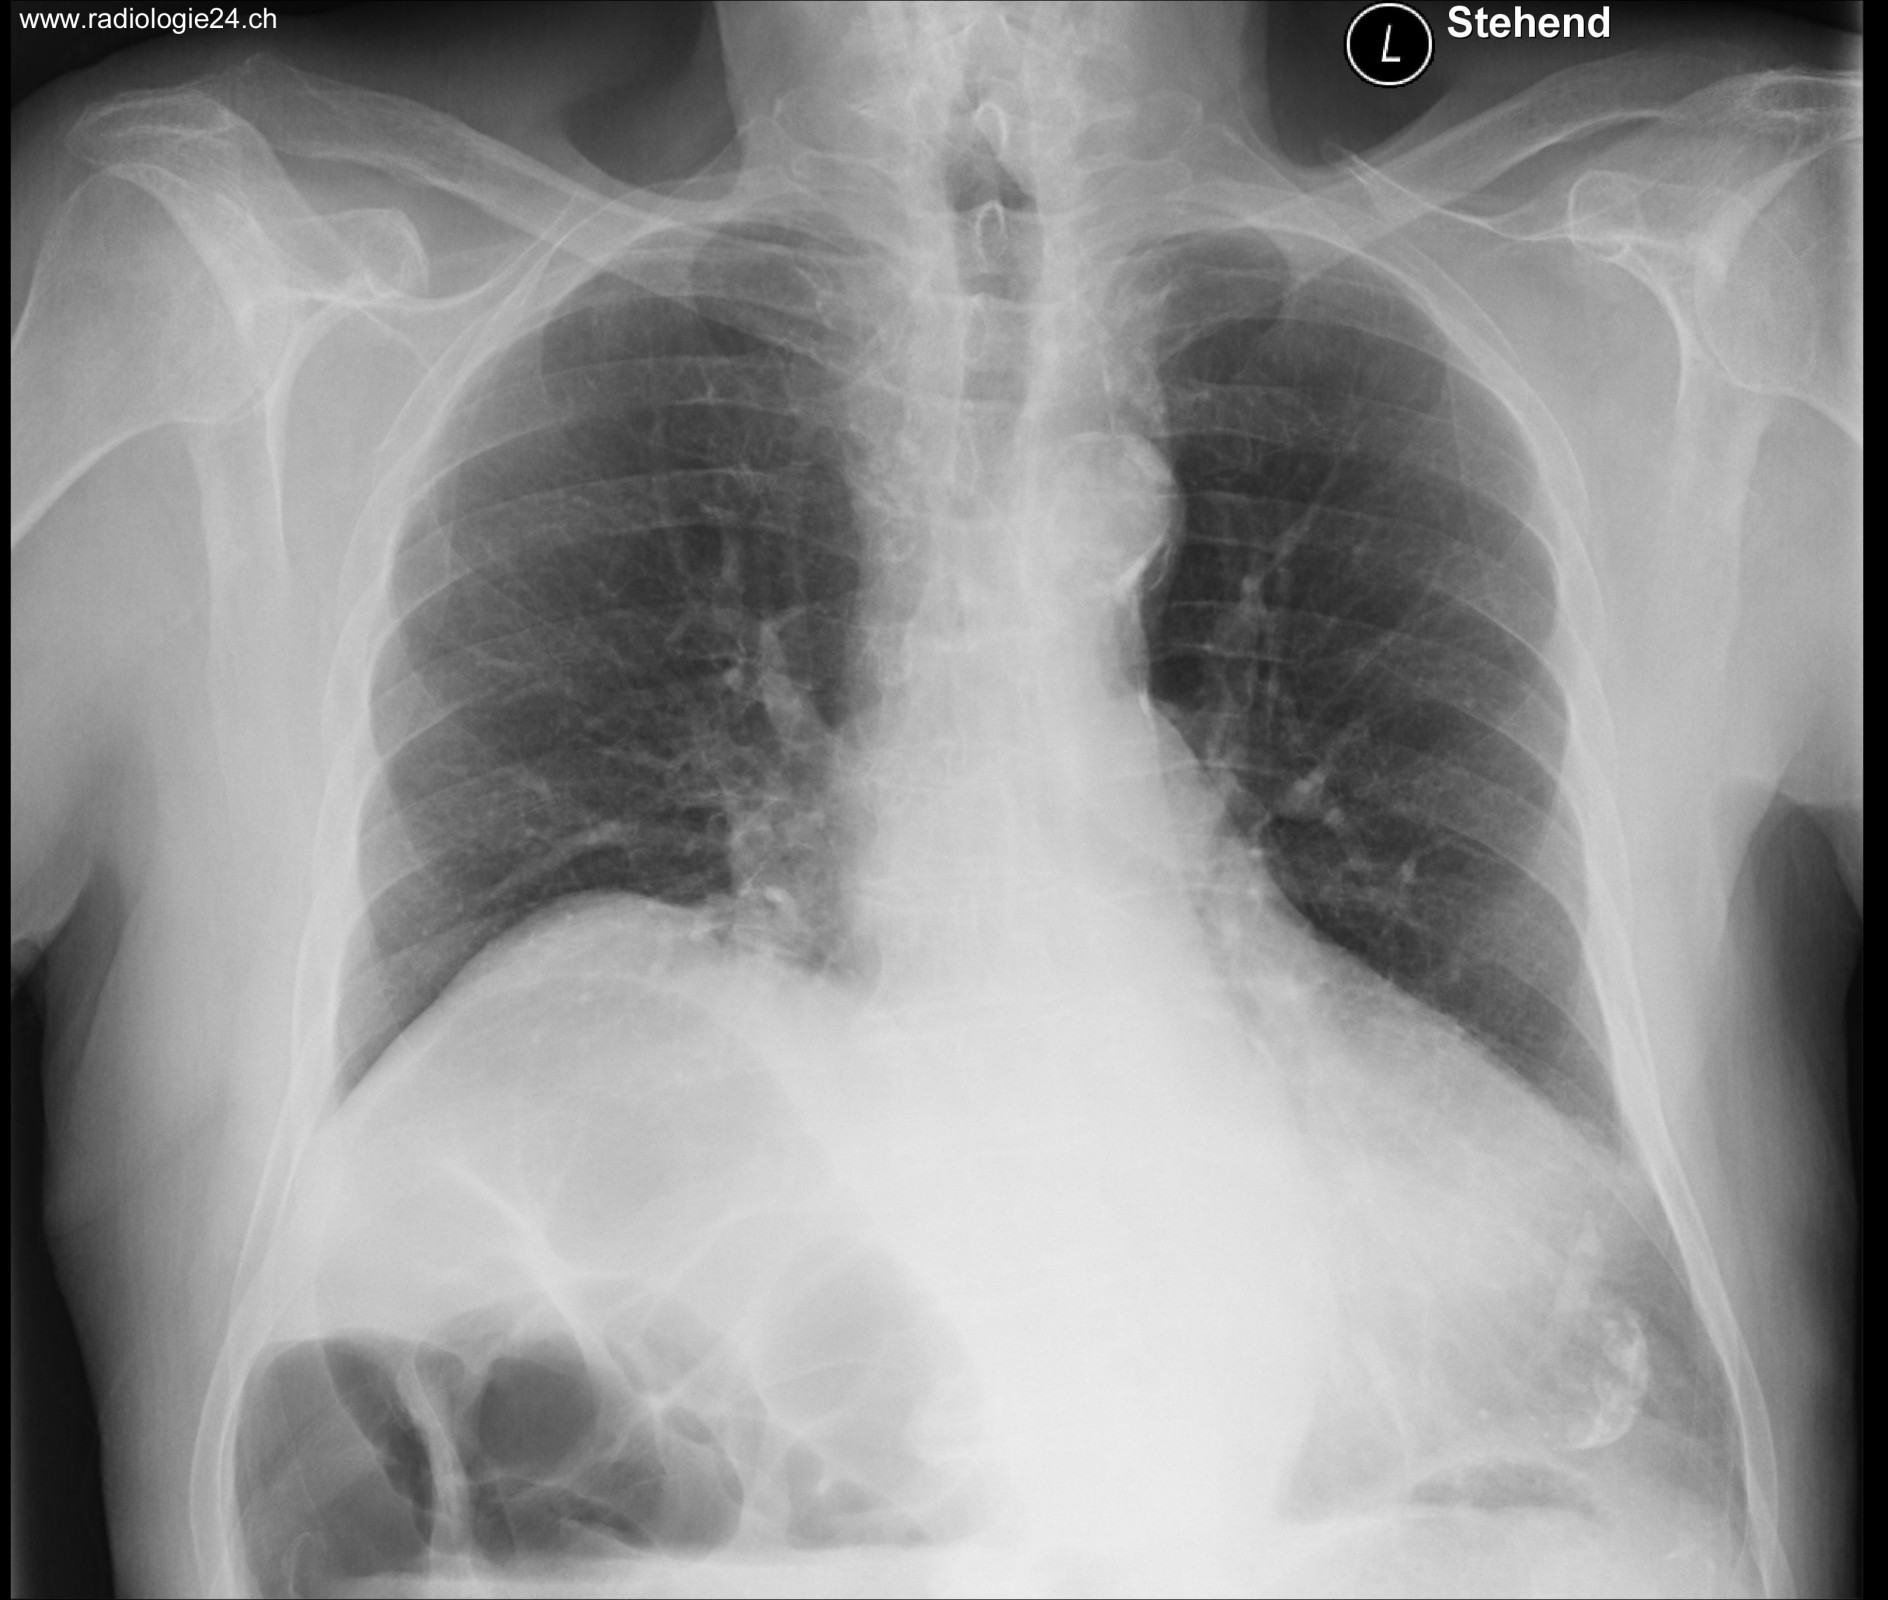

Röntgenfall des Monats Juli 2017 mit Auflösung

78 jähriger Patient mit zunehmender Dyspnoe und Thoraxschmerzen